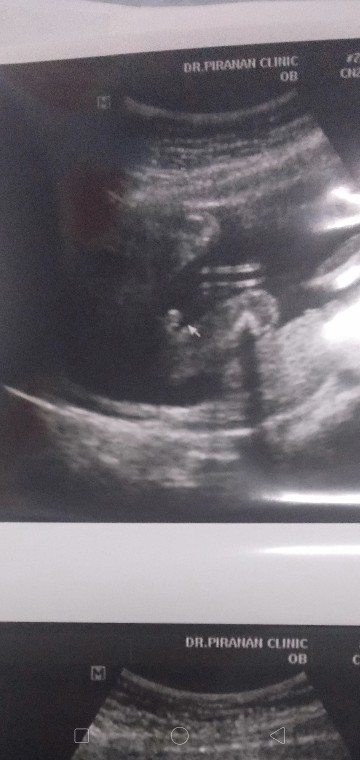

ถามแม่ๆที่มีประสบการณ์แบบนี้เพศอะไรคะแม่คุณหมอบอกว่ามีสิทธิ์ผู้หญิง 80% อันนี้รูปซาวเดือนที่แล้วค่ะเดือนนี้น้องดิ้นไม่หยุดคุณหมอเลยไม่เห็นค่ะ แม่บ้านไหน เคยไปซาวแล้วขึ้นแบบนี้บ้างคะหญิงรึชายคะ?

นี่ค่ะ ผู้ชาย จัดมากก อิอิ

ผญค่ะ ถ้า ผช แบบนี้จ้า

แลดูมีติ่งน้อยๆ

น่าจะ ญ. ค่ะแม่